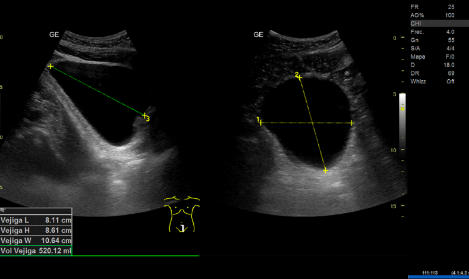

- Ecografía clínica renovesical: Vejiga sin lesiones ocupantes de espacio, sin residuo postmiccional, próstata de tamaño aumentado (56 cc). Ambos riñones con quistes corticales simples, de hasta 9,6 cm en el riñón izquierdo. Sistema excretor derecho no dilatado. Leve-moderada dilatación pielocalicial izquierda. No se evidencian imágenes ecográficas sugestivas de litiasis en pelvis renal.